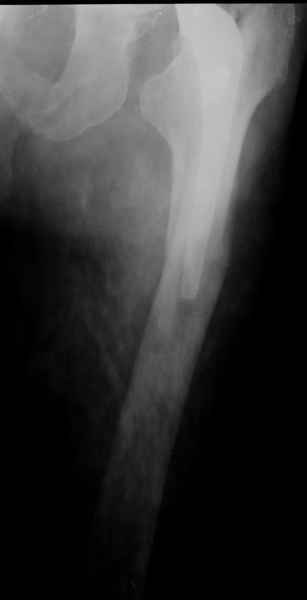

2. Применение ножки дистальной фиксации, мы отдаем предпочтение ножке Вагнера с фиксацией проксимального отдела на ножке. Более травматичное вмешательство, но при стабильной фиксации ножки реабилитация идет в обычном режиме.

Хочется показать два подобных случая, П-ка З. 72 лет и п-т Г. 80 лет. Сразу принимаю замечание, что это были ножки цементной фиксации, просто под руками не было бесцементника.